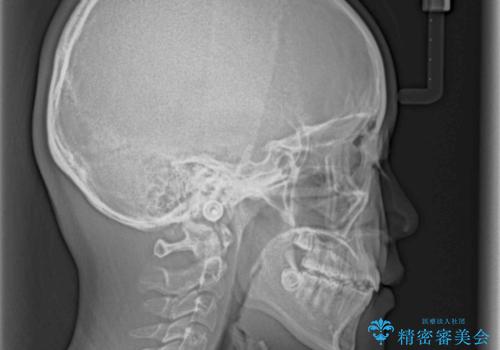

- 八重歯と乳歯が残っていることを気にして来院された患者様です。

乳歯が3歯残っており、下顎は左右ともに後続永久歯がない状態でした。

口元が突出しており、口が閉じにくかったため、乳歯を含め上下5歯を抜歯して矯正治療を行うこととしました。

下顎の乳歯は永久歯と比べて幅が大きいため、抜歯した場合のスペースが大きく、治療には長期間を要することが一般的です。

今回の患者様は中学生ということもあり、成人の患者様と比べ動きが速く、2年間で治療を終えることができました。